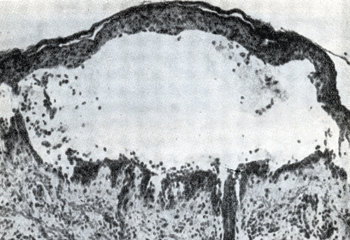

Ականտոլիզիսի հետևանքով լայնացած միջբջջային տարածություններում կուտակվում է հյուսվածքային հեղուկ, որի պատճառով լորձաթաղանթների և մաշկի մակերեսի վրա բշտեր են ձևավորվում (նկ.4):

Նկար 4. Բուշտ սովորական բշտախտի ժամանակ